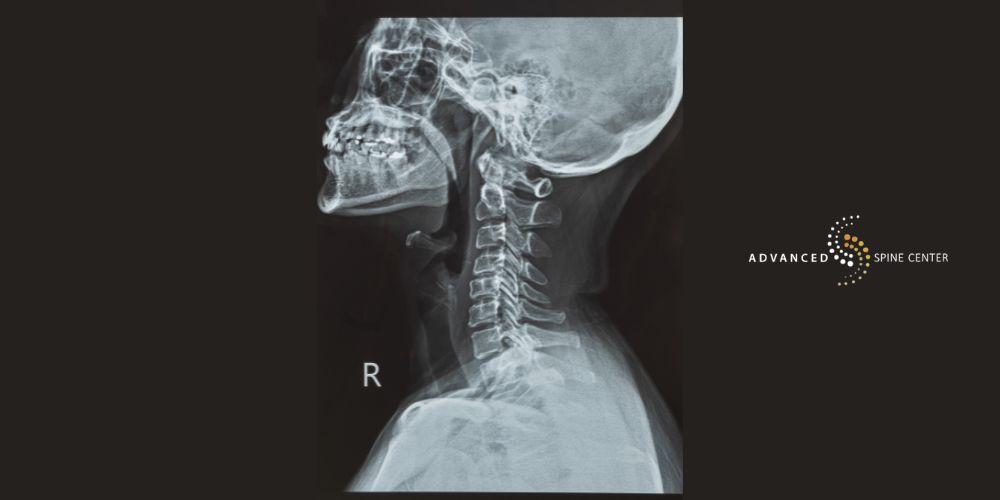

Cervical Myelopathy

Cervical myelopathy happens when the spinal cord becomes compressed in the neck, or cervical spine. This is the most common type of myelopathy. It often results from degenerative changes like spinal stenosis, disc herniation, or rheumatoid arthritis.

Symptoms of cervical myelopathy may include neck pain, weakness in the arms or hands, numbness, difficulty with coordination, and problems gripping small objects. Because the cervical spinal cord controls signals to the entire spinal cord below that level, symptoms can also extend to the lower extremities.